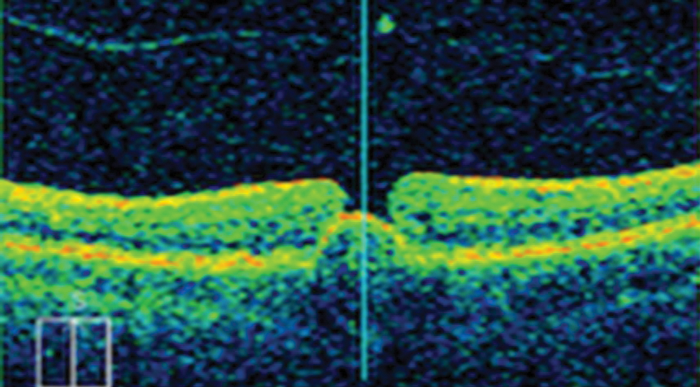

Diabetic macular oedema

In April 2013, following a rapid review submission, ranibizumab secured NICE approval as a first-line treatment for diabetic macular oedema (DMO), but only in eyes with a central retinal thickness ≥400 microns at the start of treatment [4]. Treatment with ranibizumab appears to have a superior relative effect among DMO patients with thicker retinas, explained NICE in its assessment of the evidence. The committee noted that, when compared with laser photocoagulation alone, treatment regimens that include ranibizumab are effective in improving VA over two years, but there is no evidence of additional benefit in adding laser photocoagulation to ranibizumab.